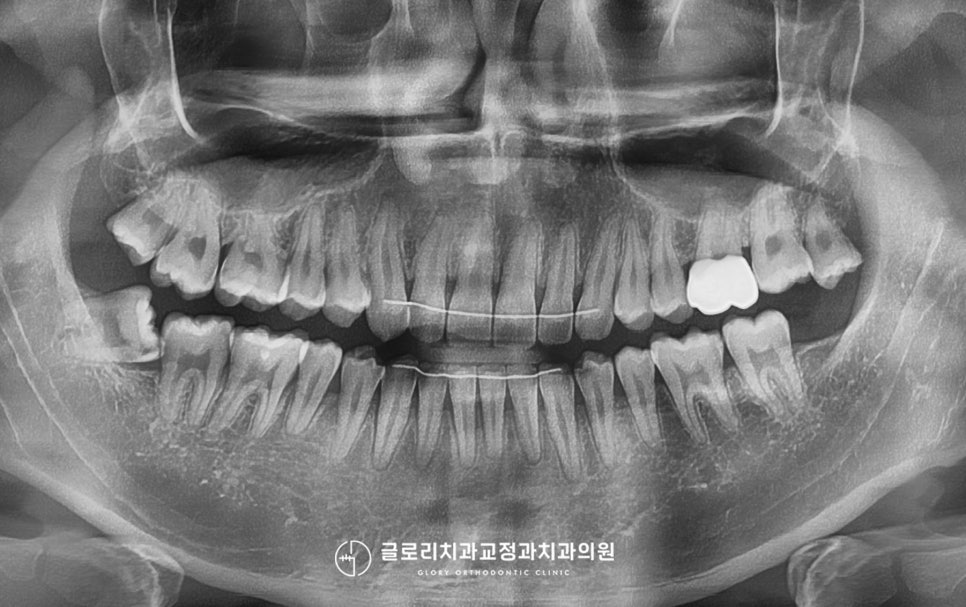

3년 전 타원에서 치료를 마치신 뒤

치열이 다시 틀어진 것 같아

저희 망우동 치과 로 찾아오셨습니다.

이 환자의 경우에는 이전 진료를 완료하신 뒤

전치부 뒤쪽에는 장치를 부착했지만

뺐다 꼈다 하여 잠을 자는 동안 끼고 있는

가철성 유지 장치인 retainer는 따로

사용을 하지 않으셨다고 하시는데요.

현재 전치부 뒤쪽으로는 이렇게

유지 장치를 부착해두셨는데요.

부착한 이후에 한 번의 철사 끊어짐이 있어

일부는 연결하지 않은 채

사용을 이어가고 계셨습니다.